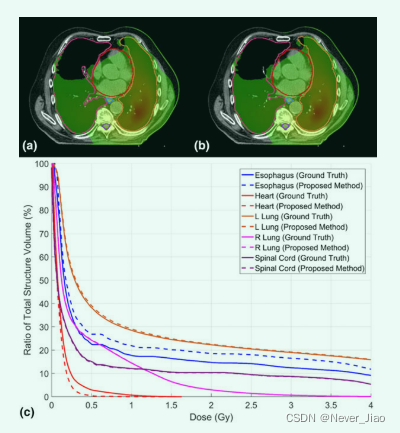

我们还评估了使用所提出的自动分割方法获得的轮廓的剂量影响。如图 7 所示,从手动轮廓获得的示例患者的所有五个 OAR 的 DVH 与所提出的方法匹配良好。 我们计算了从手动轮廓获得的所有五个 OAR 的 Dmean、D95、D50、D5、Dmin 和 Dmax 差异以及所有 20 个计划的建议方法。表 II 总结了基于真实 OAR 剂量和自动分割 OAR 剂量计算的剂量差异的平均值、标准偏差和相应的 P 值。所有 32 个剂量学指标中有 26 个显示 P > 0.05,表明ground truth OAR 和自动分割 OAR 之间没有统计学上显著的剂量差异。所有五个 OAR 的 Dmean、D95、D50、D5 和 Dmin 的平均差异均小于 0.7 Gy。平均 Dmax 差异范围为 0.06 至 1.5 Gy。 全肺D1000 cc和D1500cc的平均剂量差异均小于0.02 Gy,均P>0.05。

Fig.7 一名患者的剂量分布(a)ground truth 轮廓和(b)自动分割轮廓,以及(c)相应的剂量体积直方图。 (a) 和 (b) 的窗口宽度:0.1-1 Gy。